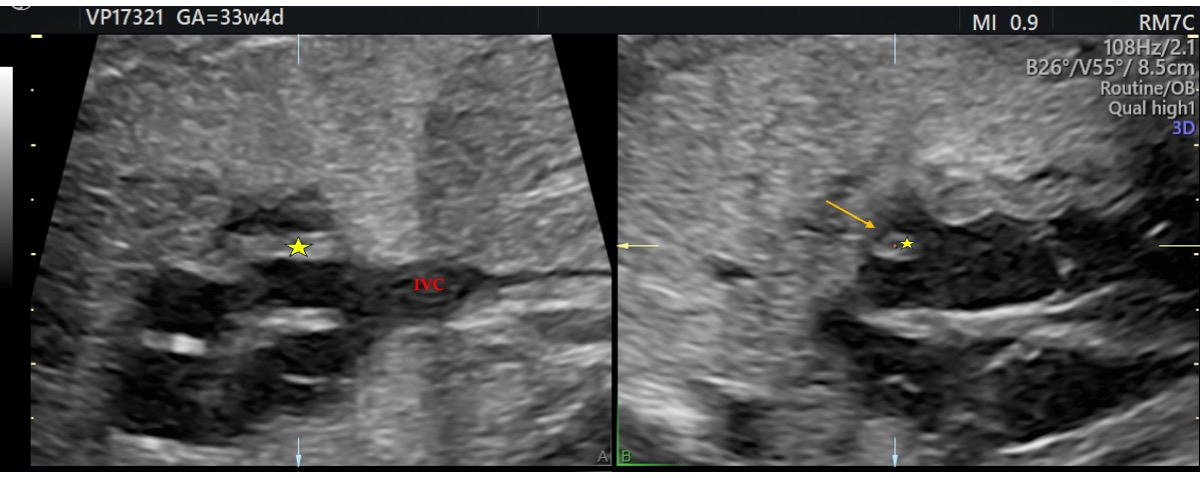

Figure 2. (A,B) Hypertrophic crista terminalis, ultrasound at 33 weeks + 4 days: a hyperechoic, round mass was seen in the right atrium (yellow arrow), which on 3D reconstruction appeared as a membranous structure traversing the atrial cavity (star). IVC: inferior vena cava.

Additionally, a thin membranous structure was observed traversing the right atrium and inserting at the superior aspect of the interatrial septum. This structure did not impede intra-atrial flow. Doppler evaluation of the ductus venosus demonstrated normal waveforms The differential diagnosis included HCT, atrial myxoma, rhabdomyoma (less likely), and intra-atrial thrombus. However, serial US executed during the remainder of the pregnancy displayed no changes in the size or characteristics of the mass (Figure 1 and Figure 2). Therefore, HCT was the favored diagnosis and no prenatal or postnatal MRI was planned. The US scans in pregnancy were defined in accordance with the most up-to-date evidence as there are no documented prenatal consequences of HCT [1]. Although there are no established guidelines for HCT, the American Heart Association and the American Society of Echocardiography (AHA/ASE) recommend repeated imaging in 2–4 weeks of the initial examination is incomplete or a progressive lesion is suspected, and the management must be individualized to the specific case [10].

Additionally, the three-vessel and trachea view (3VT), which is a transverse plane through the upper mediastinum, can help delineate the relationship of the superior vena cava and right atrial appendage—key landmarks for localizing the crista terminalis [14]. The crista terminalis originates near the superior vena cava and divides the right atrial appendage from the sinus, making these views essential for accurate anatomical assessment.